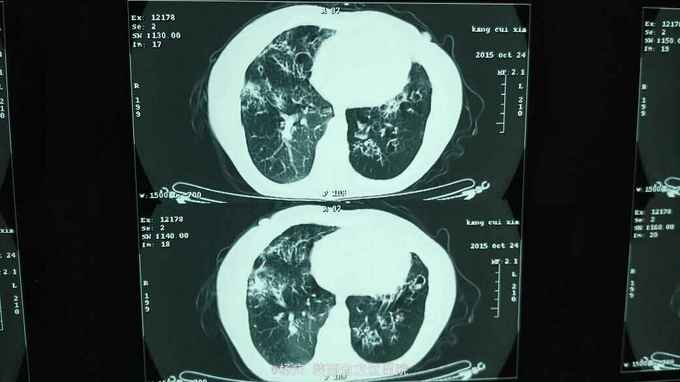

咳嗽,咳痰40年,加重1周,发热1天 40年前始反复咳嗽,咳痰,间断咯血,无声嘶、消瘦。反复多次影像学检查诊断:支气管扩张。1周前上述症状再次发作,外院静脉输液"克林霉素"常规量5天,疗效不佳。1天前出现发热,体温40.0摄氏度,发热前无发冷寒战。今被收住我院,自发病来,精神尚可,大小便正常。 既往无特殊疾病史。

TPR:39.0 80 20。血压120/80mmHg。口唇紫绀,桶状胸,双肺扣呈过轻音,双肺密集湿性啰音。心腹查体无异常。双下肢不肿。

支气管扩张并感染